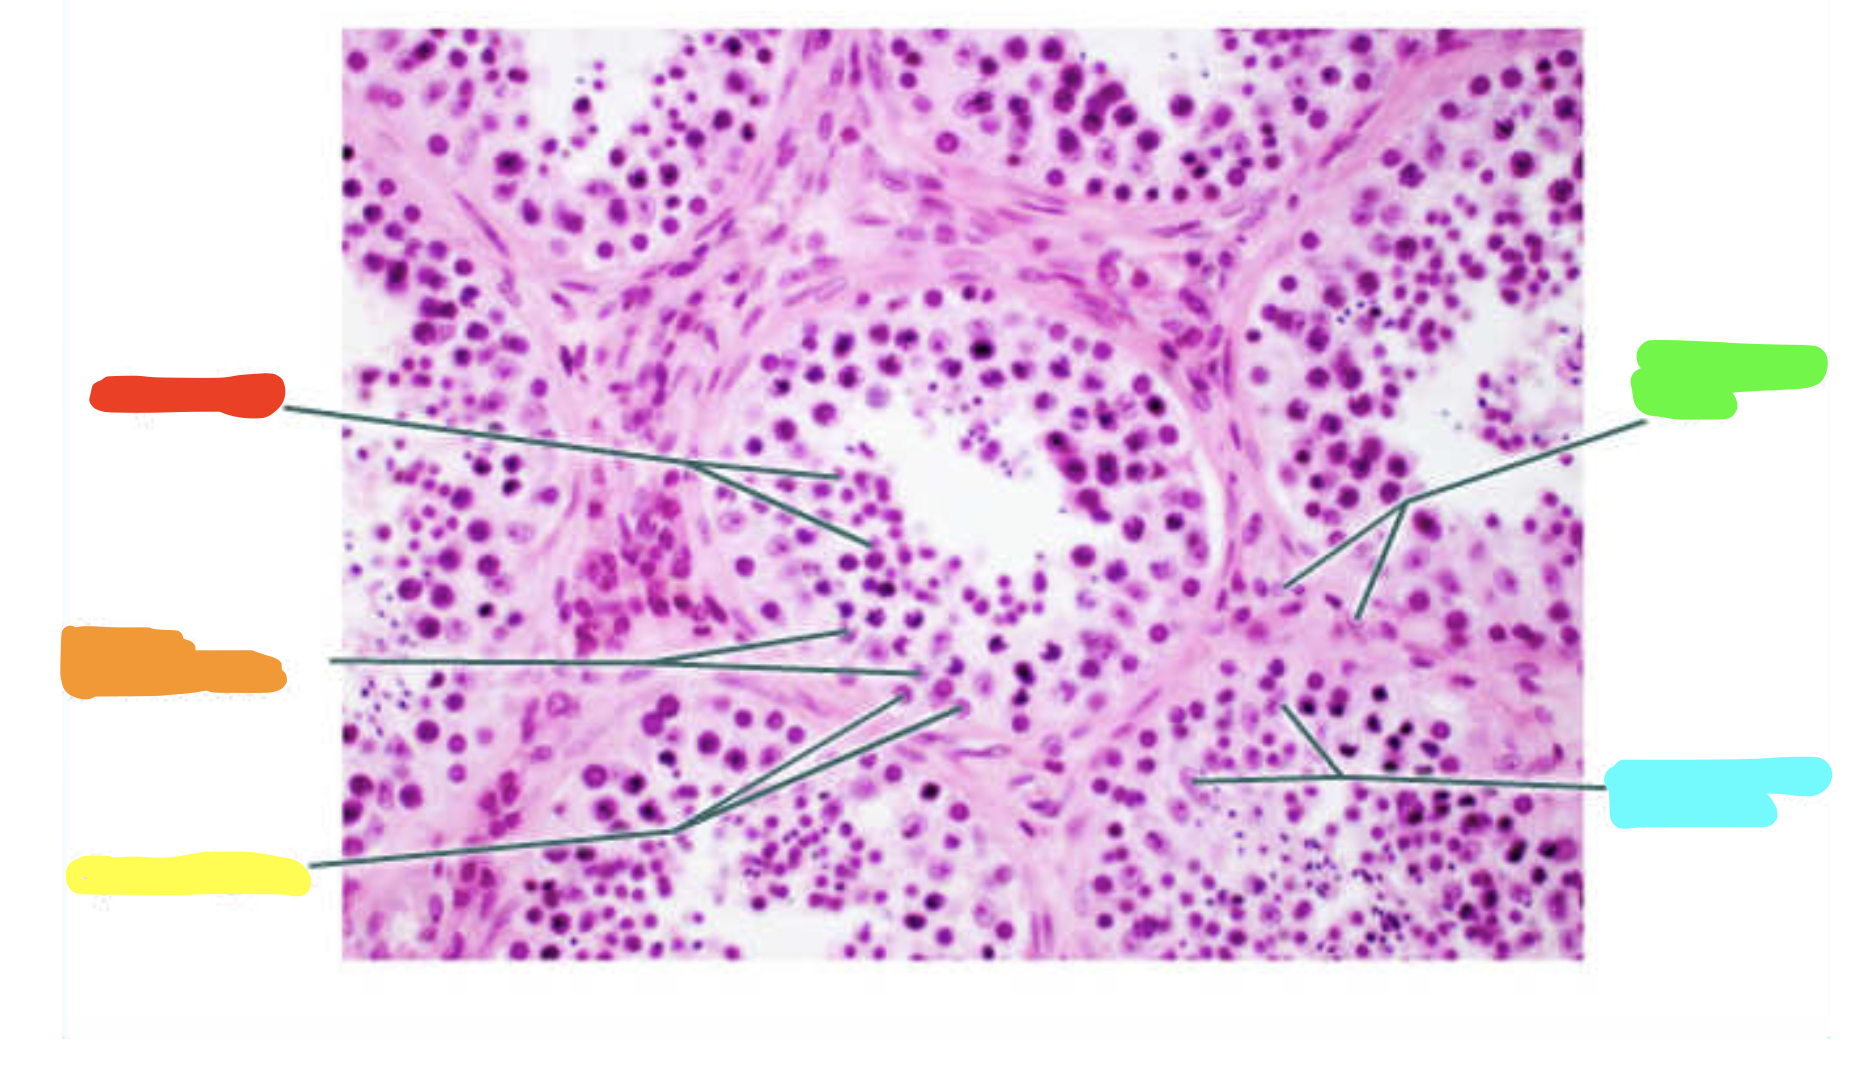

What is this a slide of?

Testis

What is red?

Seminiferous tubule

What is orange?

Primary spermatocytes

What is yellow?

Spermatogonia

What is green?

Spermatids

What is cyan?

Sustentacular cell nuclei